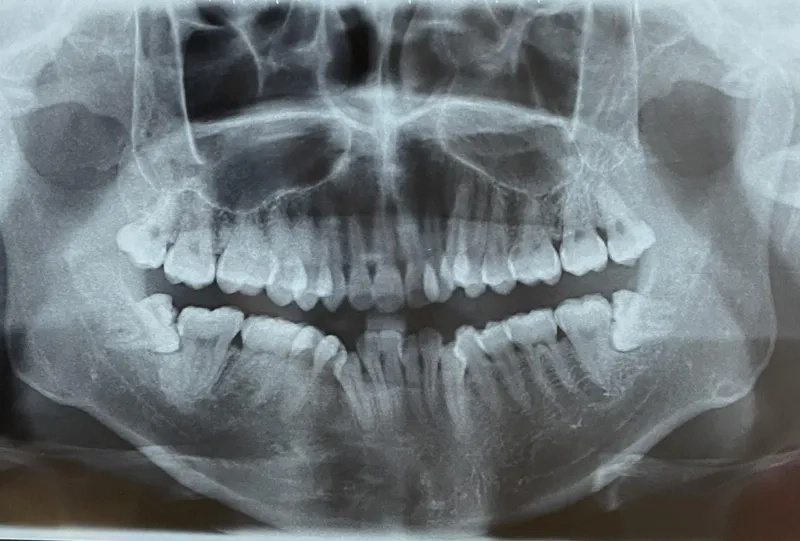

Chính vì là kẻ đến sau cùng, răng khôn thường không tìm được vị trí thuận lợi để mọc thẳng. Chúng phải tìm cách chen chúc, dẫn đến các tình trạng phổ biến như mọc lệch, mọc ngầm dưới nướu hoặc đâm ngang vào chiếc răng số 7 bên cạnh.

Hủy hoại cấu trúc răng số 7 lân cận

Khi răng khôn mọc lệch hoặc đâm ngang, nó sẽ trực tiếp húc vào chân răng số 7. Lực đẩy này diễn ra âm thầm nhưng mạnh mẽ, làm tiêu chân răng, gây sâu răng số 7 và có thể khiến chiếc răng này bị lung lay hoặc mất vĩnh viễn.

Nguy cơ hình thành u nang xương hàm

Trong một số trường hợp răng khôn mọc ngầm hoàn toàn trong xương, các mô bao quanh răng có thể phát triển thành u nang.

Nếu không được phát hiện qua phim chụp X-quang, u nang này sẽ âm thầm phá hủy xương hàm, làm tổn thương các dây thần kinh và các răng xung quanh, gây ra những tổn thương nặng nề khó phục hồi.